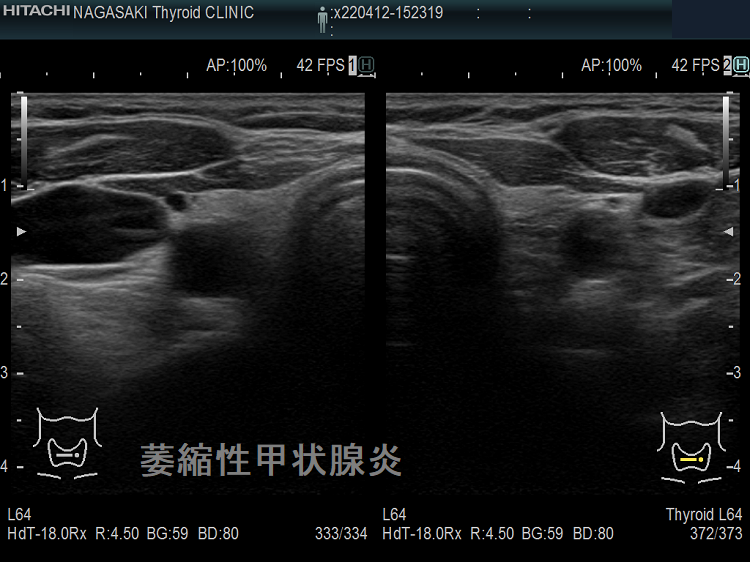

萎縮性甲状腺炎

TSBAb(TSHレセプター抗体[阻害型]、甲状腺刺激阻害抗体) が存在すると、甲状腺刺激ホルモン(TSH)が甲状腺に結合できず、甲状腺機能低下症になります(萎縮性甲状腺炎)。橋本病の破壊抗体[抗サイログロブリン抗体(TgAb)、抗甲状腺ペルオキシダーゼ抗体(TPOAb)]を同時に持っていなければ、写真の如く、甲状腺内部は正常そのものでサイズだけが萎縮します。